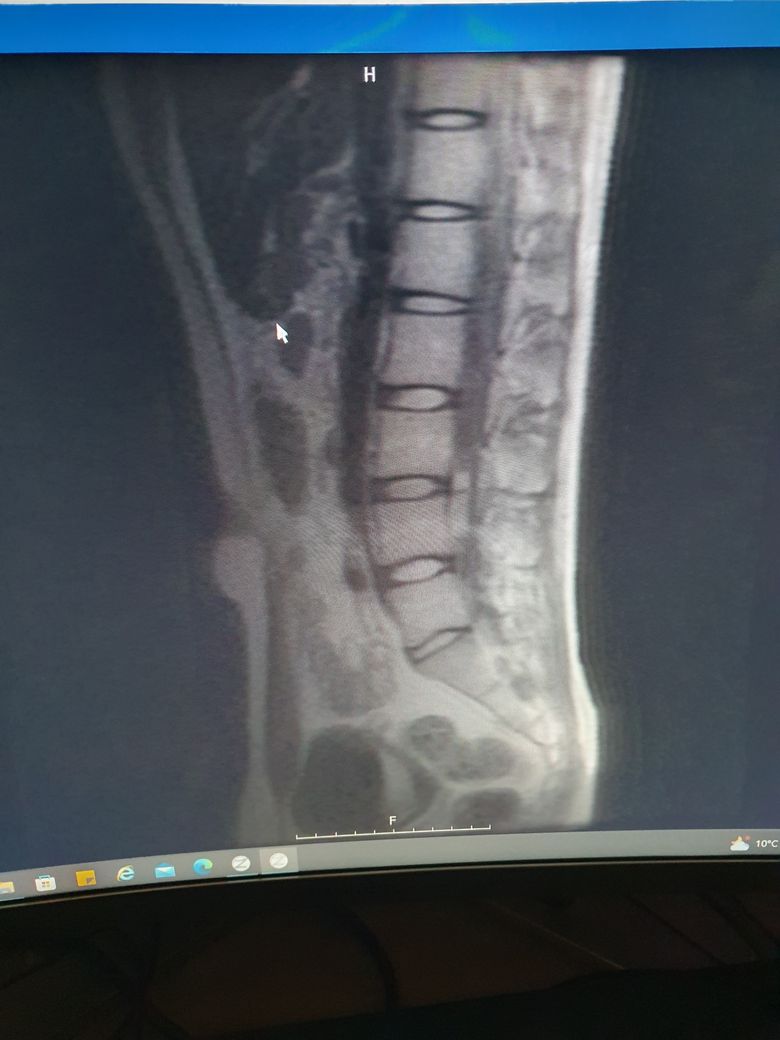

허리mri사진좀 봐주세요 ㅠㅠ만성통증

엉덩이 위쪽에전반적으로 뻐근한통증이 있습니다..ㅠ

하지 저림증상은 없구요...5번1번이 굉장히 좁은거 같은데..많이 안좋나요??

MRI로 보면 너무너무 건강한 허리입니다.

요추 5번 천추 1번 사이는 다른 요추들 사이의 디스크보다 당연히 좁아보일 수 있습니다.

지금 증상은 디스크 내장증 증상일 가능성이 있으며 요추 전만 자세만 잘 취해주시면 금방 좋아지실겁니다.